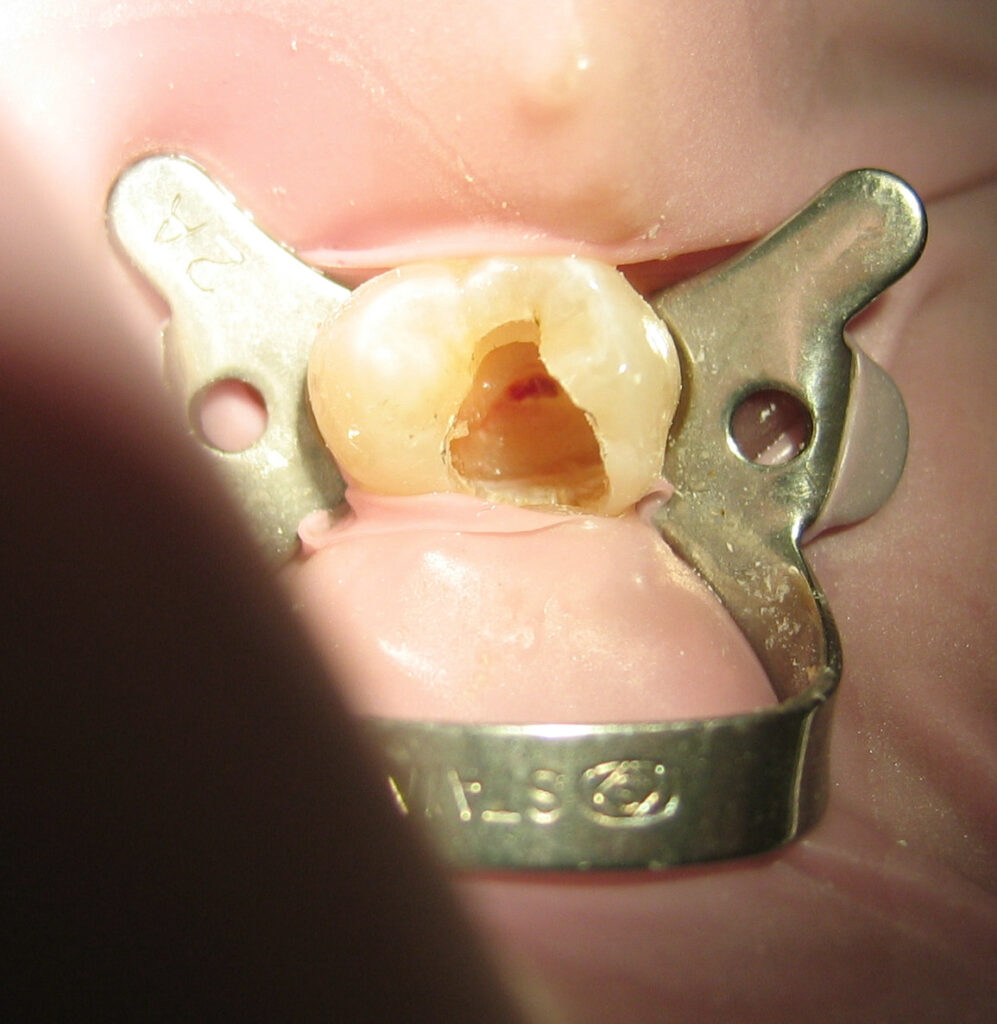

What a Root Canal Actually Does

A root canal is designed to eliminate pain, not cause it.

It treats:

- Infected tooth pulp

- Deep decay

- Dental abscess

- Trauma to the tooth

The dentist removes the inflamed nerve tissue, cleans the inside of the tooth, and seals it — stopping the pain source entirely.